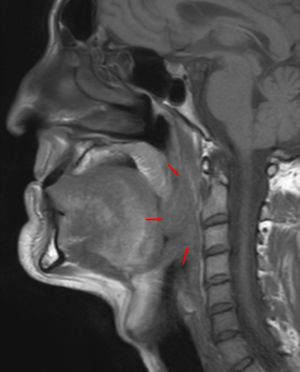

구인두암은 구인두에 발생하는 암으로, 2주 이상 지속되는 인후통, 목의 통증, 체중 감소, 쉰 목소리, 귀의 통증 등의 증상을 보인다. 흡연, 과도한 음주, 인유두종 바이러스(HPV) 감염 등이 주요 위험 요인이며, 과일과 채소 섭취 부족, 빈랑 씹기, 대마초 흡연, 석면 노출 등도 위험 요인으로 작용할 수 있다. 진단은 조직 생검을 통해 이루어지며, 암의 크기, 림프절 전이 여부, 다른 부위로의 전이에 따라 병기가 결정된다. 예방을 위해 HPV 백신 접종, 안전한 성관계, 금연, 절주 등이 권장된다. 치료는 수술, 방사선 치료, 항암 화학 요법 등을 병행하며, HPV 양성 구인두암 환자의 예후가 더 좋은 경향이 있다.

구인두암 진단은 구인두에서 관찰되는 비정상 조직에 대한 생검을 통해 이루어진다.